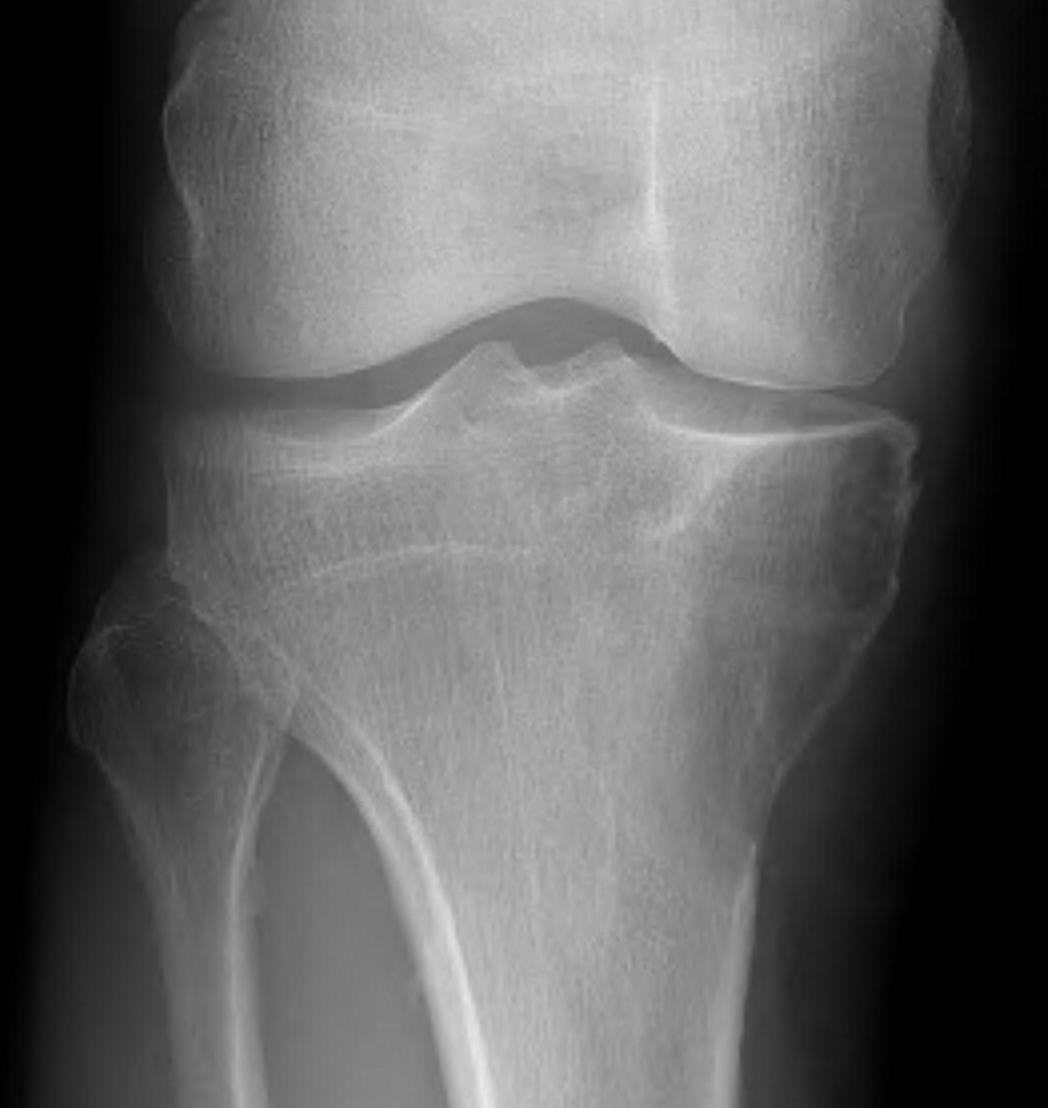

X-ray

Well defined eccentrically located epiphyseal lesion

- thin sclerotic reactive rim

- may have calcification

- 26% proximal tibia

- 22% distal femur